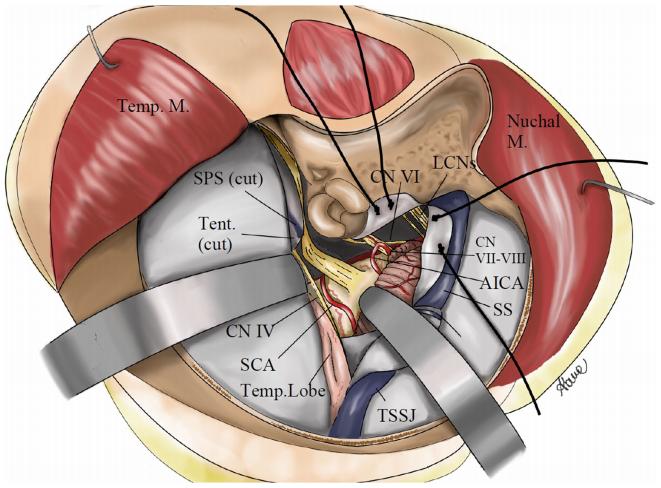

两次手术,两种不同的手术入路,都致力于实现微创和全切。在深思熟虑之下,福教授决定采用内镜经鼻入路+mini经岩骨入路,而后者正是福教授及团队为减少损伤而改良后的版本。其目的是尽力减少对软组织的剥离,从而降低入路的侵袭性,患者恢复更快,同时提供与经典联合岩骨入路相似的手术暴露,最后手术缝合关闭时也更方便复位。

两个月后,潇潇的身体恢复良好,于是,福教授又为她进行了Ⅱ期手术。这一次采取的是右侧的mini经岩骨入路,最终实现全切,且无任何新发神经功能缺损。